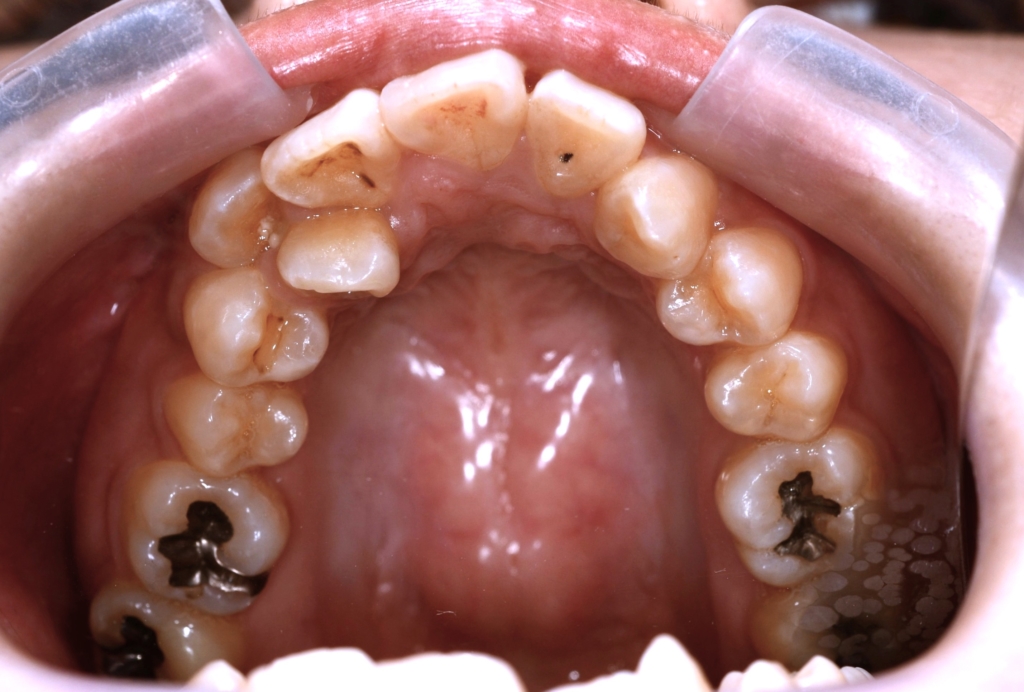

【抜歯】

通法通り上下の左右の奥歯(第一小臼歯)を1本ずつ計4本の便宜抜歯

【治療装置】

マルチブラケットシステム(スタンダードtype)で矯正を開始

アンカースクリュー

(上顎の口蓋に2本使用)